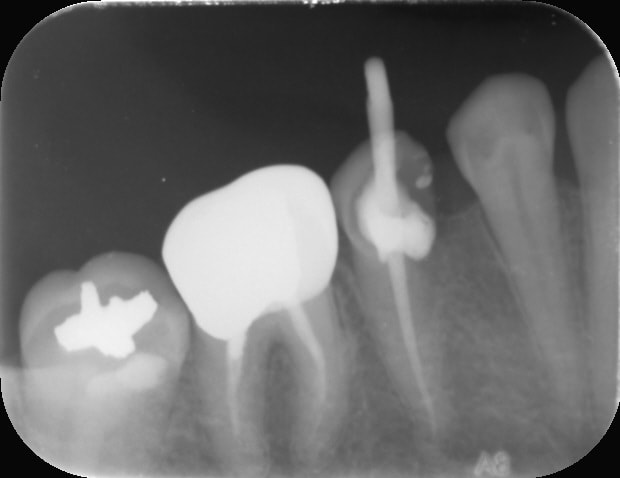

Tiens celle ci c'est pour le plaisir d'offrir et c'est pour Vulpi qui avait l'air de se moquer de moi hier😊:

-> cas d'aujourd'hui

- dent calcifiée comme jamais

- je réussis à retrouvé le canal au niveau des 3/4 de la dent avec un insert endo fin (radio avec insert ci joint)

- obturation quasi Ă  l'apex

- rĂ©alisĂ© avec un capodent et non une digue😊😊😊

Ah c'est dommage! La 6 a une couronne non adaptée en distal (premiÚre RX il y a la reconstitution qui déborde, c'est pas étanche) et probablement une indication de RTE, la 5 non conservable à long terme, 4 en pilier antérieur dent vivante, voilà une belle indication de bridge :-)))